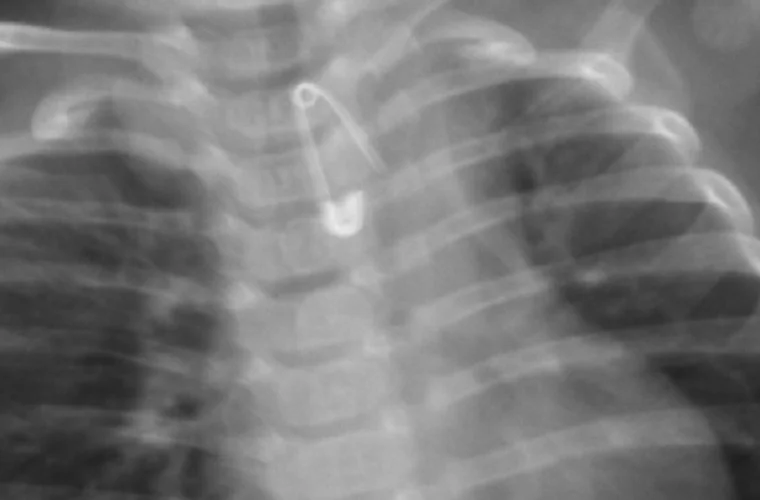

Rodzice z 6-miesięcznym Kubusiem natychmiast wsiedli w samochód i pojechali do szpitala w Krotoszynie. I choć - jak wykazało zdjęcie rentgenowskie - malec połknął 2-centymetrową agrafkę, która, rozwarta, skierowana była ostrzem w dół w przełyku chłopca - lekarka pełniąca dyżur w Szpitalnym Oddziale Ratunkowym w Krotoszynie kazała rodzicom zawieźć chłopca do szpitala w Ostrowie Wlkp.

Na miejscu wykonano badanie RTG przełyku i jamy brzusznej, które potwierdziło obecność w przełyku ciała obcego. Po wykonaniu tego badania, pełniąca wówczas dyżur oskarżona lekarka, nie wykonując dalszej diagnostyki i nie zapoznając się z dokumentacją medyczną chłopca, poleciła rodzicom przetransportowanie chłopca do Szpitala w Ostrowie Wielkopolskim ich prywatnym samochodem - tłumaczył Krzysztof Bukowiecki, rzecznik prasowy prokuratury regionalnej w Łodzi.